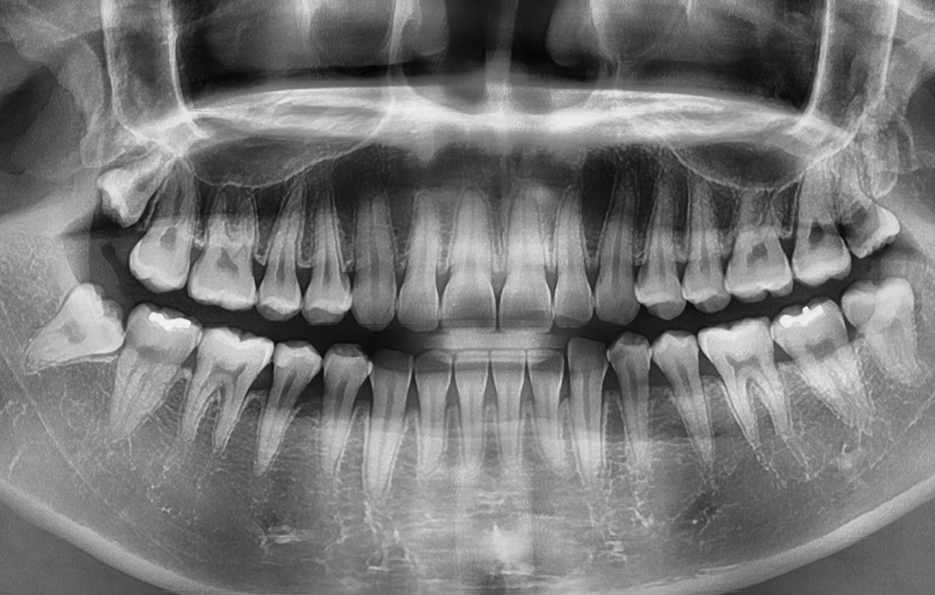

사랑니는 사람마다 다르게 생겼다고 알고는 계시겠지만 실질적으로 어떻게 생겼고 구분되는지 잘 모르시는 분들도 많을 거예요. 사랑니의 모양을 기준으로 형태를 나눠보면 똑바로 정상 맹출된 사랑니와 부분적으로 매복되어 있는 사랑니, 완전 매복되어 있는 모양으로 구분할 수 있는데요.

완전 매복되어 있는 사랑니 중에서는 어금니 쪽 방향으로 누워서 자라는 경우도 있고 어금니의 반대방향으로 누워 자라기도 하며 완전히 수평으로 매복되어 있기도 하고 수직으로 매복되어 있는 경우로도 또 다시 분류할 수 있어요.

동일한 조건이라고 가정할 때 사랑니의 모양에 따라 발치 난이도가 달라져요

사랑니 발치에 있어서 사랑니가 충치로 인해 썩었거나 현재 잇몸이 붓고 염증이 발생한 상황과 같이 특정 상황적 조건을 무시하고 사랑니의 모양만을 두고 발치 난이도를 구분해보자면 당연하게도 정상적으로 맹출된 사랑니가 보다 뽑기 쉽다고 할 수 있겠고 반면에 완전 매복되어 있는 사랑니의 경우 보다 발치의 어려움을 느낄 수 있는데요

위 환자분의 사랑니 케이스를 살펴보면 윗니의 경우 정상 맹출된 사랑니의 형태를 보이지만 아랫니의 경우에는 부분 매복되어 있고 누워서 자라고 있는 사랑니의 형태를 볼 수 있어요. 다 그런 것은 아니지만 윗니의 경우 중력에 의해 정상 맹출된 사랑니의 형태가 좀더 많다면 아랫니의 경우 매복사랑니의 형태가 많은 편이기 때문에 하악 사랑니의 발치가 좀더 어려운 경우가 있어요